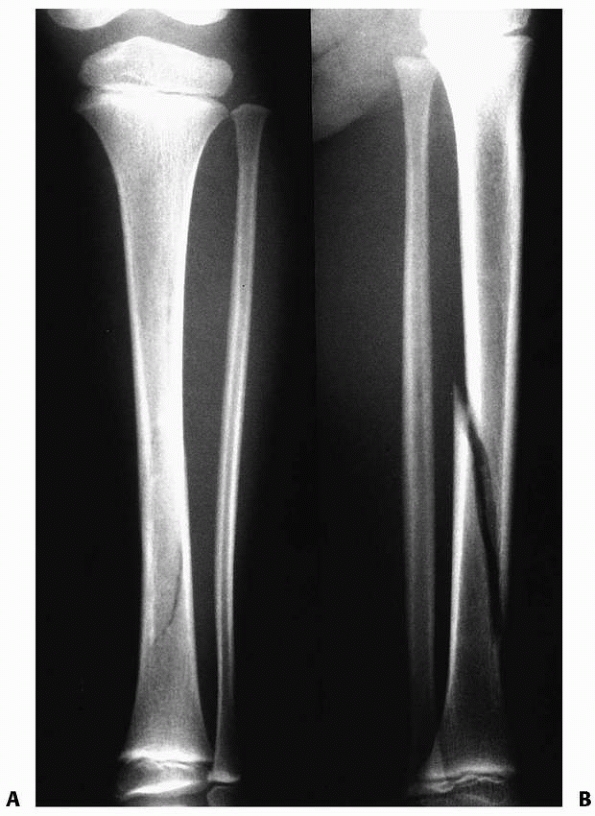

FIGURE 25-29 A,B. Unstable distal metadiaphyseal fractures of the tibia and fibula in a 15-year-old girl. C. This fracture was stabilized with percutaneous pins because of marked swelling and fracture instability.

|